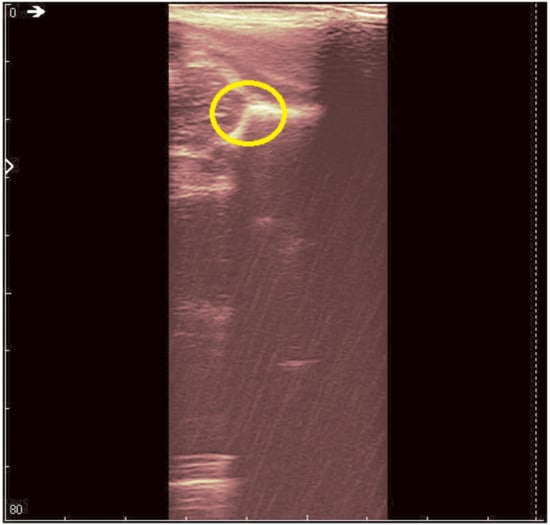

An ultrasound (Image 3 (Figure 10 and Figure 11)) was taken of a male patient with a sample frequency of 7.5 MHz and a frame rate of 29 fps. The parameters are same as in the previous two cases, yet the image of the acetabulum is hardly visible.

After applying the HWT filtering (Figure 12), the acetabulum, the femoral head, and the femur can be outlined by any physician.

We may conclude, when comparing last two images, that after filtering several details can be seen, easing the process of diagnosis for a trained physician. The denoised images are brighter and more details (not visible on the original image) can be distinguished.

Figure 10. Original data, Image 3.